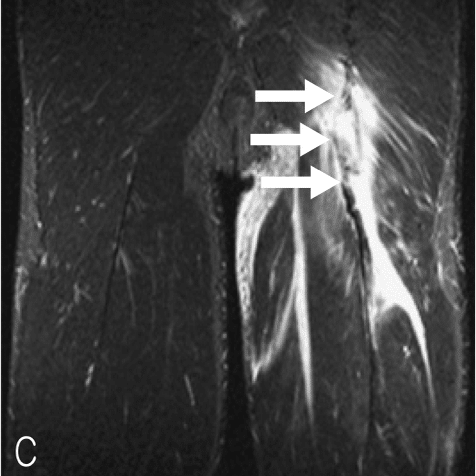

◉損傷後の修復が得られにくい大腿二頭筋遠位部損傷

(Distal Musculotendinous T Junction:DMTJ)

(Entwisle T, Ling Y, Splatt A, Brukner P, Connell D. Distal Musculotendinous T Junction Injuries of the Biceps Femoris: An MRI Case Review. Orthop J Sports Med. 2017 から引用)